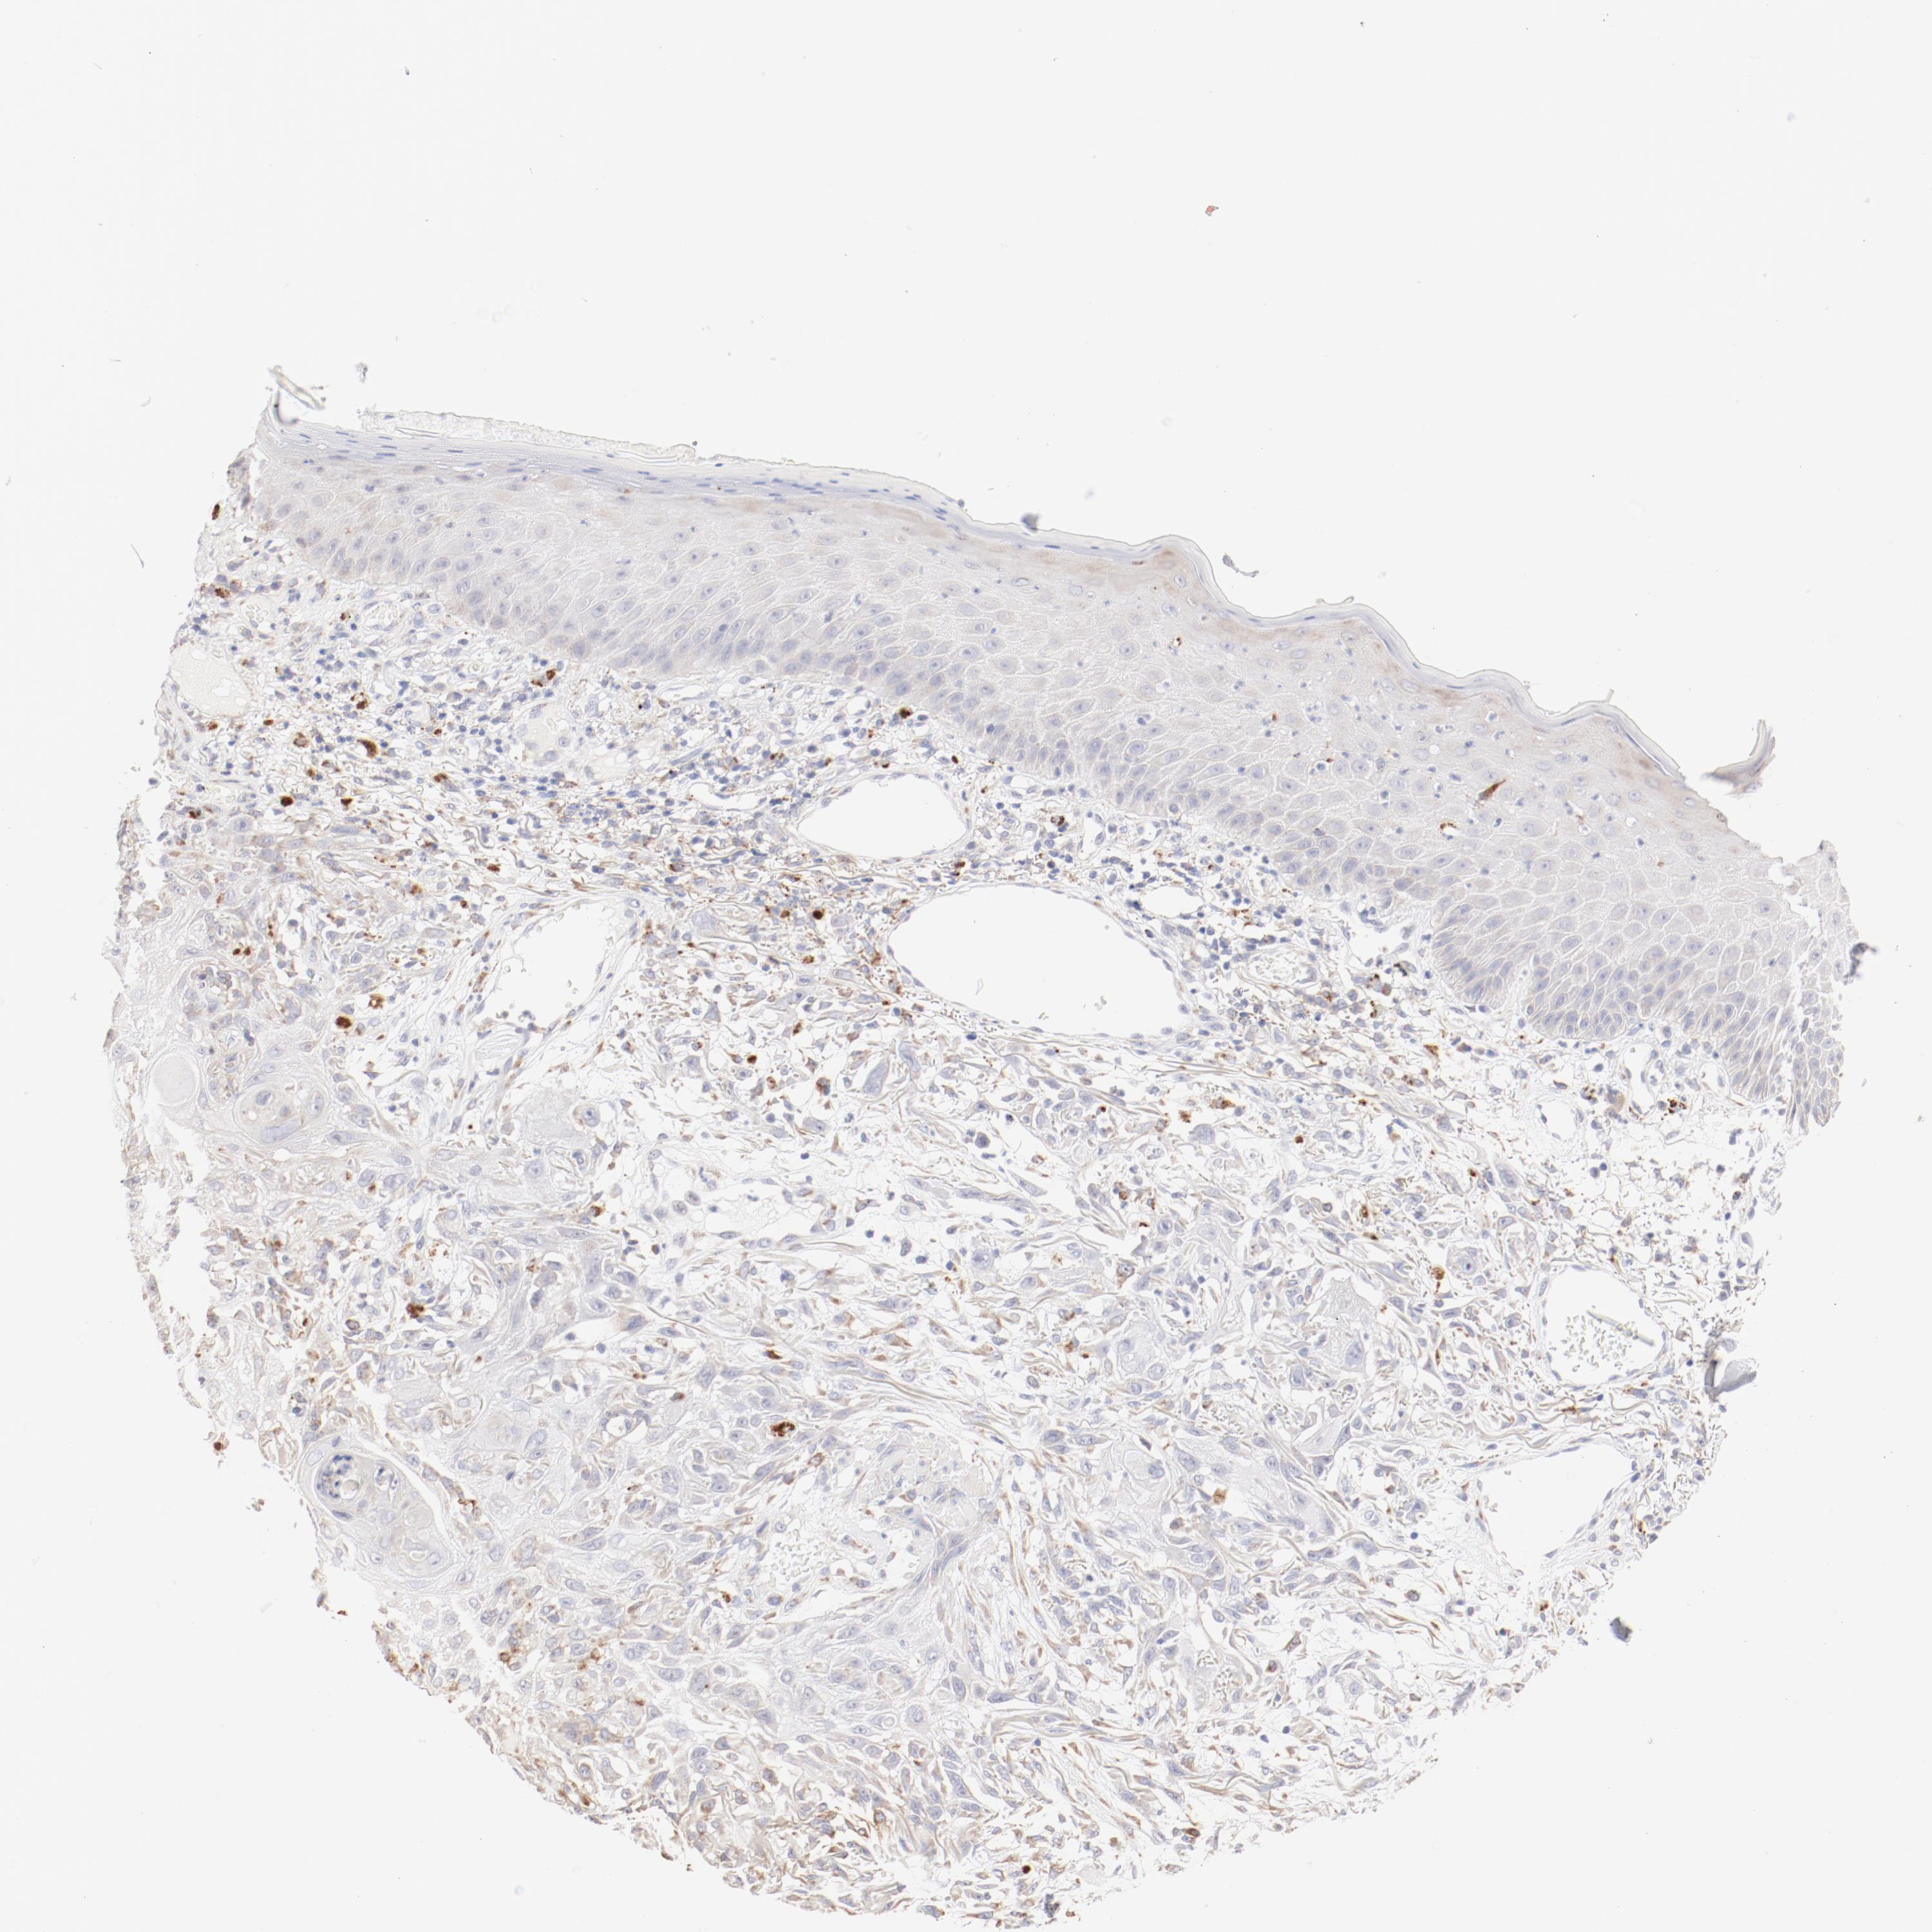

Basal cell and squamous cell cancer

SKIN CANCER - Protein expressioni

A mouse-over function shows sample information and annotation data. Click on an image to view it in a full screen mode. Samples can be filtered based on level of antibody staining by selecting one or several of the following categories: high, medium, low and not detected. The assay and annotation is described here.

Antibody stainingi

Antibody staining in the annotated cell types in the current human tissue is reported as not detected, low, medium, or high, based on conventional immunohistochemistry profiling in selected tissues. This score is based on the combination of the staining intensity and fraction of stained cells.

Each image is clickable and will lead to virtual microscopy that enables deeper exploration of all samples and also displays staining intensity scores, fraction scores and subcellular localization as well as patient and tissue information for each sample.

Antibody CAB000458

Staining

High

Intensity

Strong

Quantity

>75%

Location

Nuclear

Basal cell carcinoma